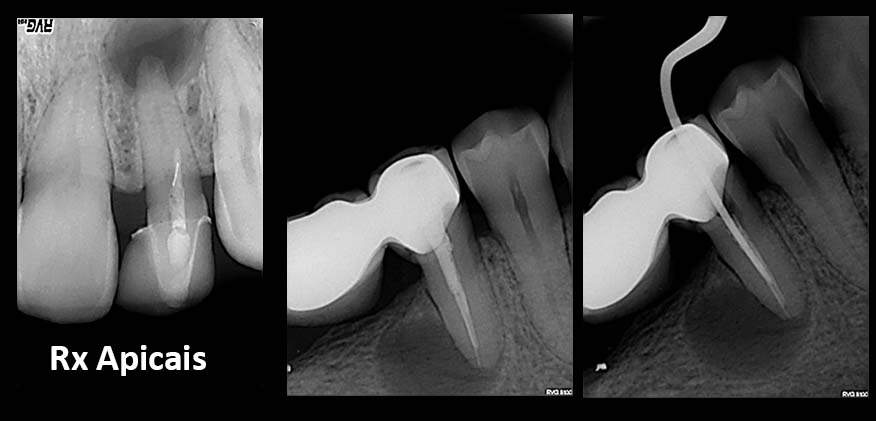

• Radiographies/X´Rays

Urgent treatments are executed if necessary as in the case on the left.

SOS